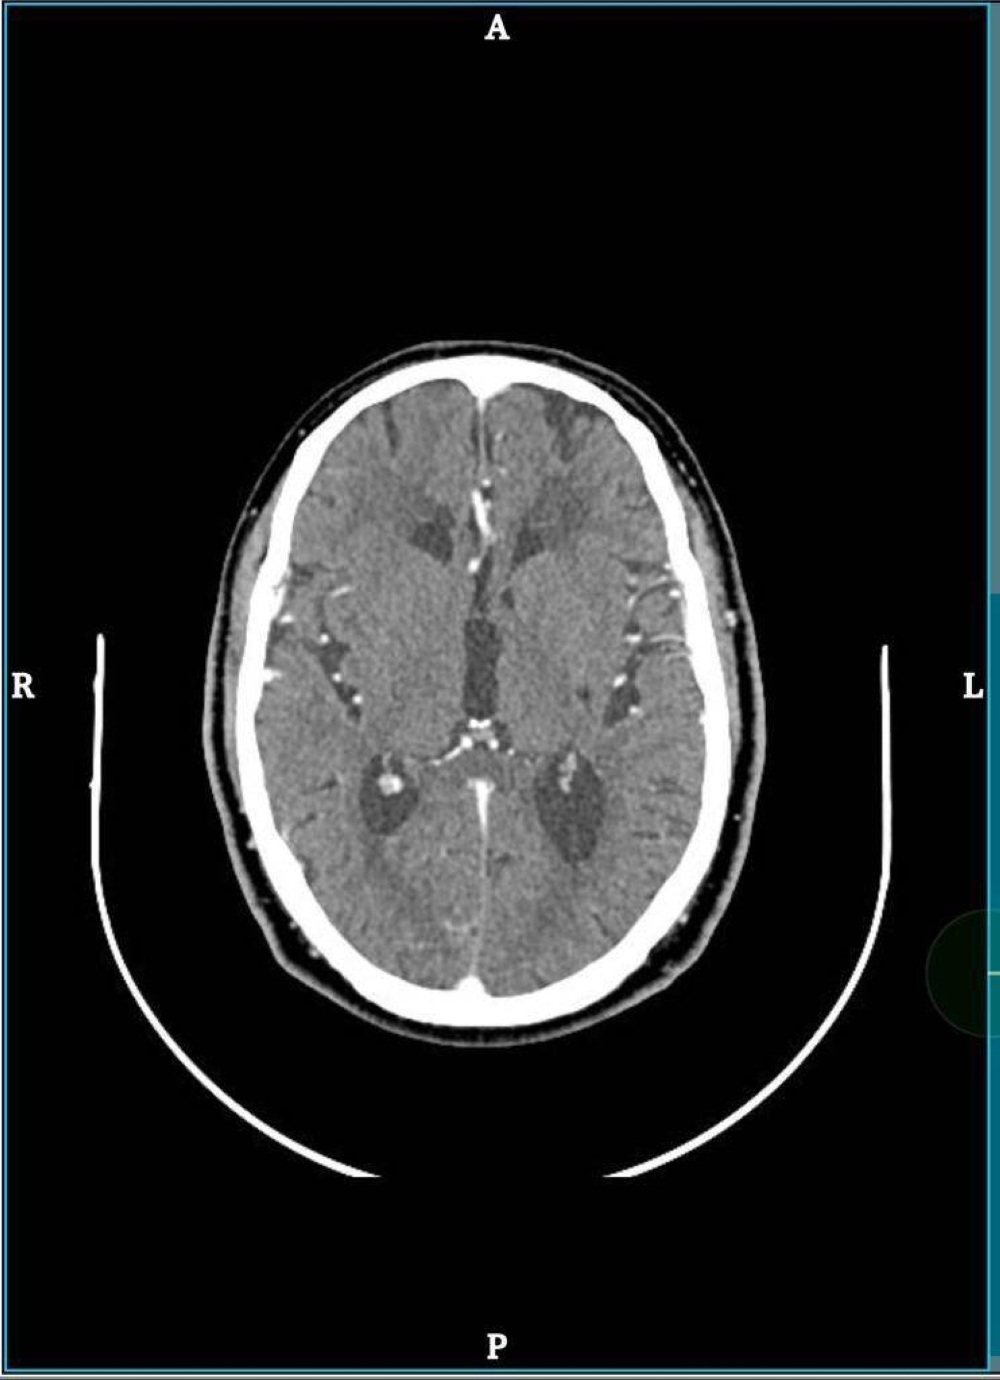

وقال مدير مستشفى الملك خالد بالمجمعة، الدكتور خالد القحطاني، إن المريض توجه للطوارئ وهو يعاني من ضعف الجانب الأيسر من جسمه وصعوبة بالكلام، وبعد تشخيص حالته بواسطة الفريق الطبي والتمريضي بالطوارئ وفريق الجلطة الدماغية، تم نقله إلى العناية المركزة لإعطائه الدواء العاجل في مثل هذه الحالات عن طريق خدمة الطب الاتصالي .

وبين القحطاني، أن المستشفى فعّل مسار الجلطات الدماغية، باستخدام الطب الإتصالي (TELE-STROKE) بالتعاون مع تجمع الرياض الصحي الثاني حيث تتم المعالجة تحت إشراف مباشر من استشاريين متخصصين في مجال الجلطات الدماغية .